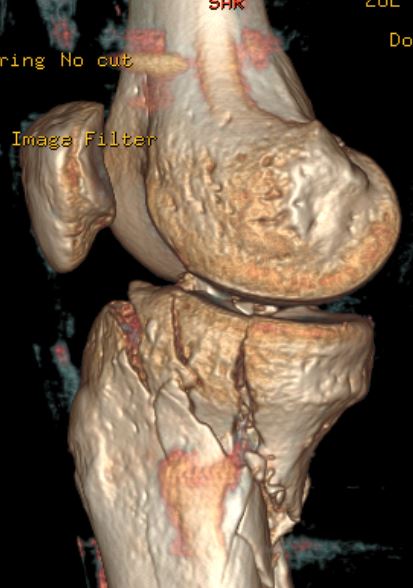

Das ist genau das große Problem, Kniegelenk ist zertrümmert, auch die Kreuzbänder, Kapsel und alles drumherum, ist schwer verletzt, hoffentlich kann ich es genug dehnen um weiter zu falten, jetzt bin ich nur bei 114° unter extremer Spannung, locker bin ich bei 104°, und übe schon vom 3-7-21, 3/Woche Fisio und den Rest 3 mal/Tag Hausübungen, hoffe bis April wieder fit zu sein um zu fahren... und Gute Nacht